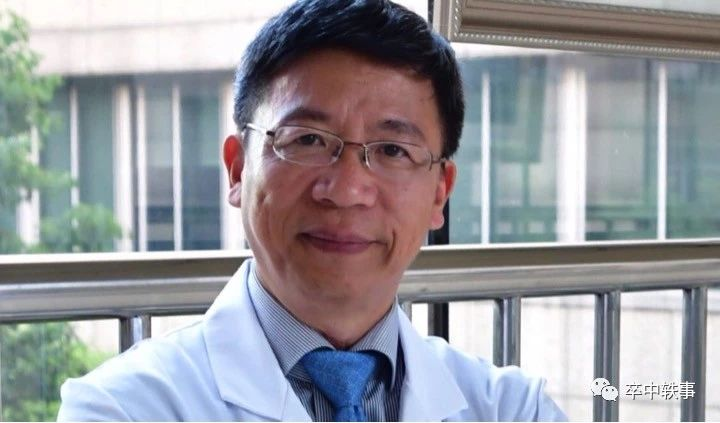

浙江大学医学院二附院神经外科的张建民(上图)教授说,后循环动脉瘤手术一直是神经外科手术的 “珠峰”,极具挑战性且充满风险,所以敬佩 Drake 大无畏的开创精神。

现有证据显示血管内治疗后循环动脉瘤优于手术夹闭,但显微夹闭手术对有些后循环动脉瘤仍然有优势。此外,宽颈动脉瘤、夹层及瘤内血栓形成、位于动脉远段或瘤壁有血管发出时,血管内治疗困难,容易复发,采用血流重建手术效果更理想。

张教授指出,血管内和手术都是治疗后循环动脉瘤的有效方式,必须由手术和介入医生共同评估,实施个性化治疗方案。此外,术中荧光造影,复合手术室及介入材料的改进也将大大提高后循环动脉瘤的治疗水平。